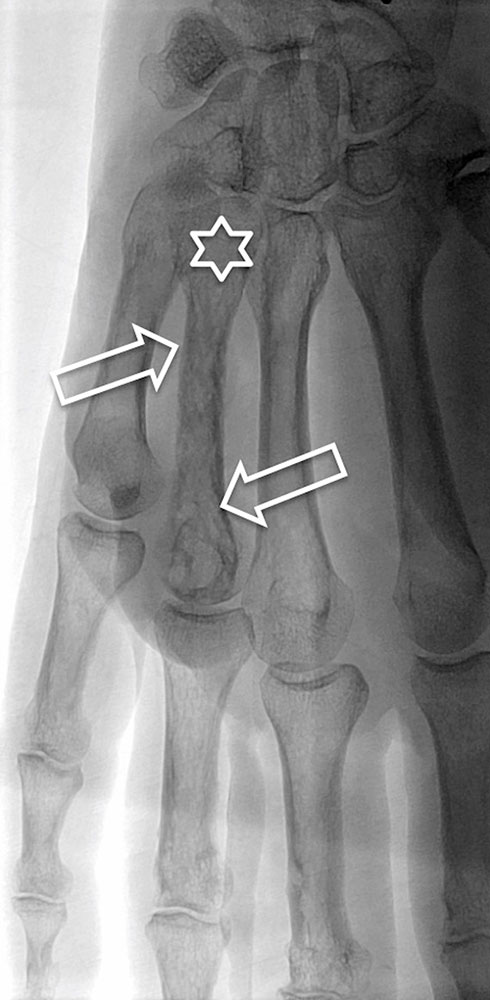

In addition, cross-sectional imaging using computed tomography (CT) or magnetic resonance imaging (MRI) is required to confirm the diagnosis, localization and involvement of organs. CT with contrast agent administration plays a lesser role in this context: it can easily detect bony involvement of the arteriovenous malformation, but spread to soft tissues is better visualized by MRI. The hemodynamics of the lesion can also be visualized by dynamic, contrast-enhanced MR angiography. In MRI, so-called flow voids are present in sequences without contrast medium because of the rapid blood flow. The dilated arteries supplying the nidus ("feeder arteries") usually follow a tortuous course. Depending on the angioarchitecture, single dominant dilated veins or several more net-like dilated veins can be delineated as the outflow of the lesion. The surrounding tissue may show edematous or fibrous-fatty changes. Involved bony structures may exhibit lytic changes or hyperplasia.